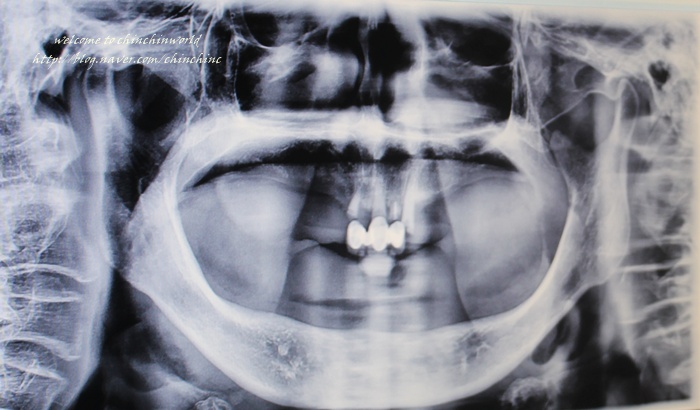

Àá½Ã ÈÄ X-ray½Ç¿¡¼ ÃÔ¿µÇØ¿ä

±äÀåÇÑ ±Í¿°µÕÀÌ ¤»¤»¤»¤»¤»¤»¤»

¾ÆºüÀÇ ¿¢½º·¹ÀÌ »çÁøµµ º¸°í

´Ù¸¥ Ä¡·á ÀÚ·áµµ º¸¿©´Þ¶ó°í ÇÏ½Ã´Ï ¸¹ÀÌ º¸¿©Áּ̾î¿ä

ÀÌ ºÐÀº À̰¡ ¸¹ÀÌ ¾øÀ¸¼Ì´ø ºÐÀε¥ ÀÓÇöõÆ® ÈÄ

Ʋ´Ï¸¦ ÀåÂøÇϼ̴õ¶ó±¸¿ä